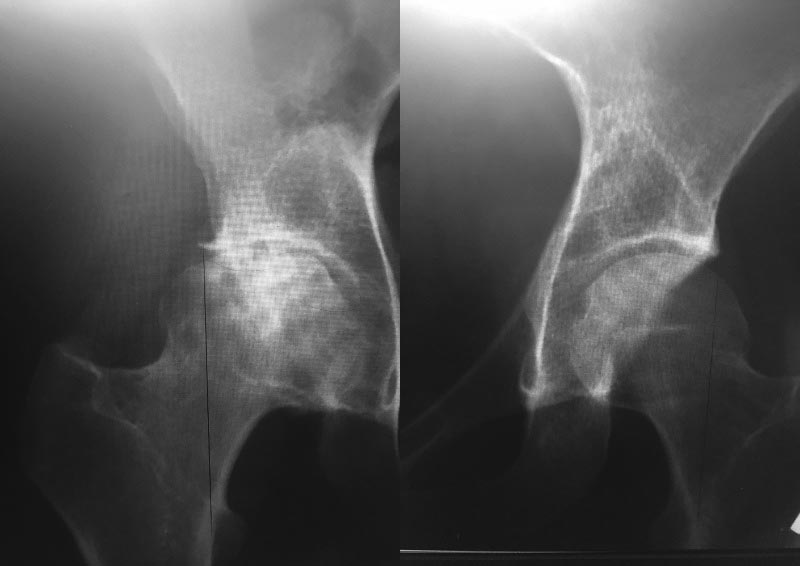

[Ortho] Дислпстический коксартроз ІІІ степени у молодой пациентки

Ещё снимки. Почему-то при сканировании качество на выходе ужасное